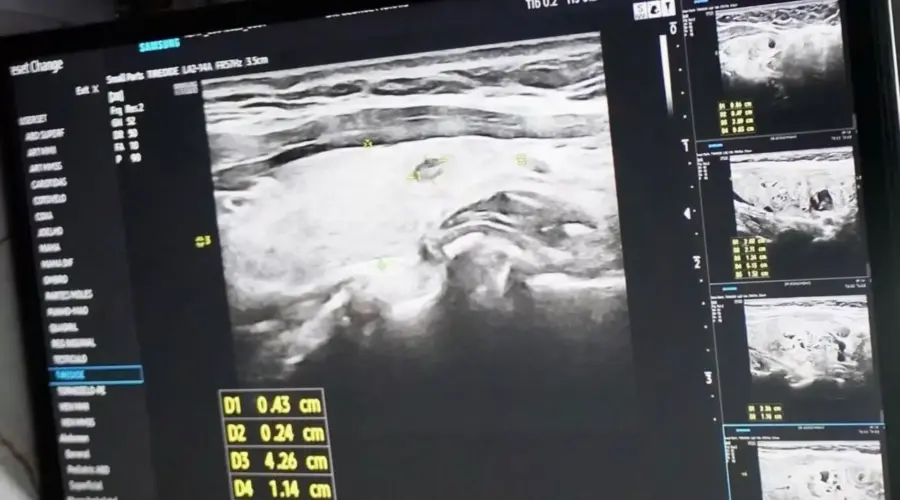

O ônibus da saúde foi a estrutura central do mutirão. Estacionado em ponto estratégico da cidade, o veículo recebeu cerca de 300 pessoas ao longo do dia. Médicos e técnicos realizaram ultrassonografias, avaliações clínicas e encaminhamentos para a rede pública.

Pacientes com alterações detectadas saíram com orientações e agendamentos para acompanhamento especializado, reduzindo o tempo de espera por diagnóstico.

A iniciativa reforça a importância do rastreio precoce da doença, que muitas vezes é silenciosa. Segundo especialistas que participaram da ação, identificar nódulos e alterações hormonais ainda em estágio inicial aumenta de forma significativa as chances de tratamento eficaz. A equipe também distribuiu material informativo e tirou dúvidas da população sobre sintomas, fatores de risco e prevenção.